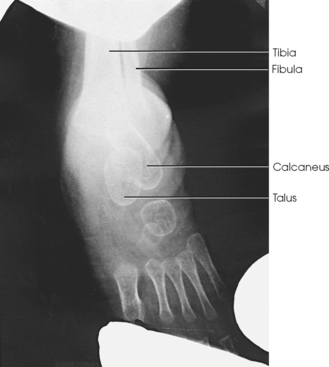

The ankle joint is commonly called the ankle mortise, or mortise joint. It is formed by the articulations between the lateral malleolus of the fibula and the inferior surface and medial malleolus of the tibia (Fig. 6-13, A). The mortise joint is often divided specifically into the talofibular and tibiofibular joints. These form a socket type of structure that articulates with the superior portion of the talus. The talus fits inside the mortise. The articulation is a synovial hinge type of joint. The primary action of the ankle joint is dorsiflexion (flexion) and plantar flexion (extension); however, in full plantar flexion, a small amount of rotation and abduction-adduction is permitted. The mortise joint also allows inversion and eversion of the foot. Other movements at the ankle largely depend on the gliding movements of the intertarsal joints, particularly the one between the talus and calcaneus.

The fibula articulates with the tibia at its distal and proximal ends. The distal tibiofibular joint is a fibrous syndesmosis joint allowing slight movement. The head of the fibula articulates with the posteroinferior surface of the lateral condyle of the tibia, which forms the proximal tibiofibular joint, which is a synovial gliding joint (see Fig. 6-13, A).

Structures shown: The image shows a true AP projection of the ankle joint, the distal ends of the tibia and fibula, and the proximal portion of the talus.

NOTE: The inferior tibiofibular articulation and the talofibular articulation are not “open” or shown in profile in the true AP projection. This is a positive sign for the radiologist because it indicates that the patient has no ruptured ligaments or other type of separations. For this reason, it is important that the position of the ankle be anatomically “true” for the AP projection shown (Fig. 6-92).

Structures shown: The resulting image shows a true lateral projection of the lower third of the tibia and fibula; the ankle joint; and the tarsals, including the base of the fifth metatarsal (Figs. 6-94 and 6-95).